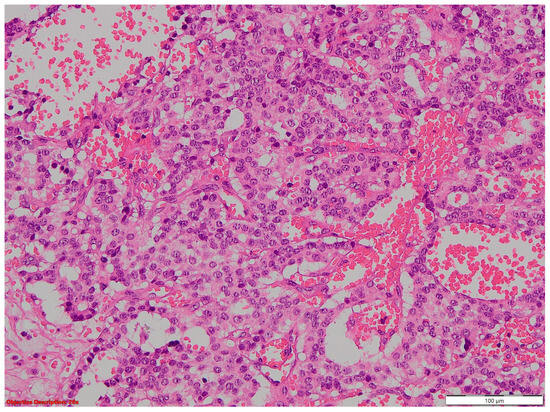

Two of the specimens with fibronodular lesions were associated with multiple NSCLC tumors of different histopathological subtypes: one case presented with adenocarcinoma (one tumor—Figure 6) and a squamous cell tumor (one tumor—Figure 7) and another case presented with adenocarcinoma (one tumor) and large-cell neuroendocrine tumors (two tumors—Figure 8).

Figure 6. Lung adenocarcinoma: (a) gross examination (white tumor with polycyclic contour and anthracotic deposits); and (b) microscopic examination (tumoral glands that replace the normal lung parenchyma); HE, 40×.